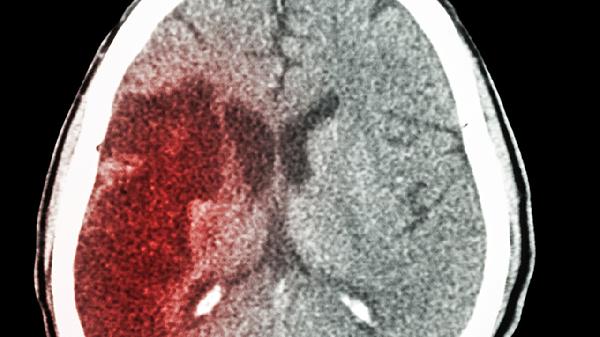

中老年脑动脉硬化患者出现慢性头晕、头重脚轻感时,脑立清丸可辅助改善脑供血。这类患者多伴有记忆力减退、睡眠障碍等表现。用药期间需控制血脂血糖,避免与抗凝药同用。出现肢体麻木或言语不清等中风先兆时禁用。